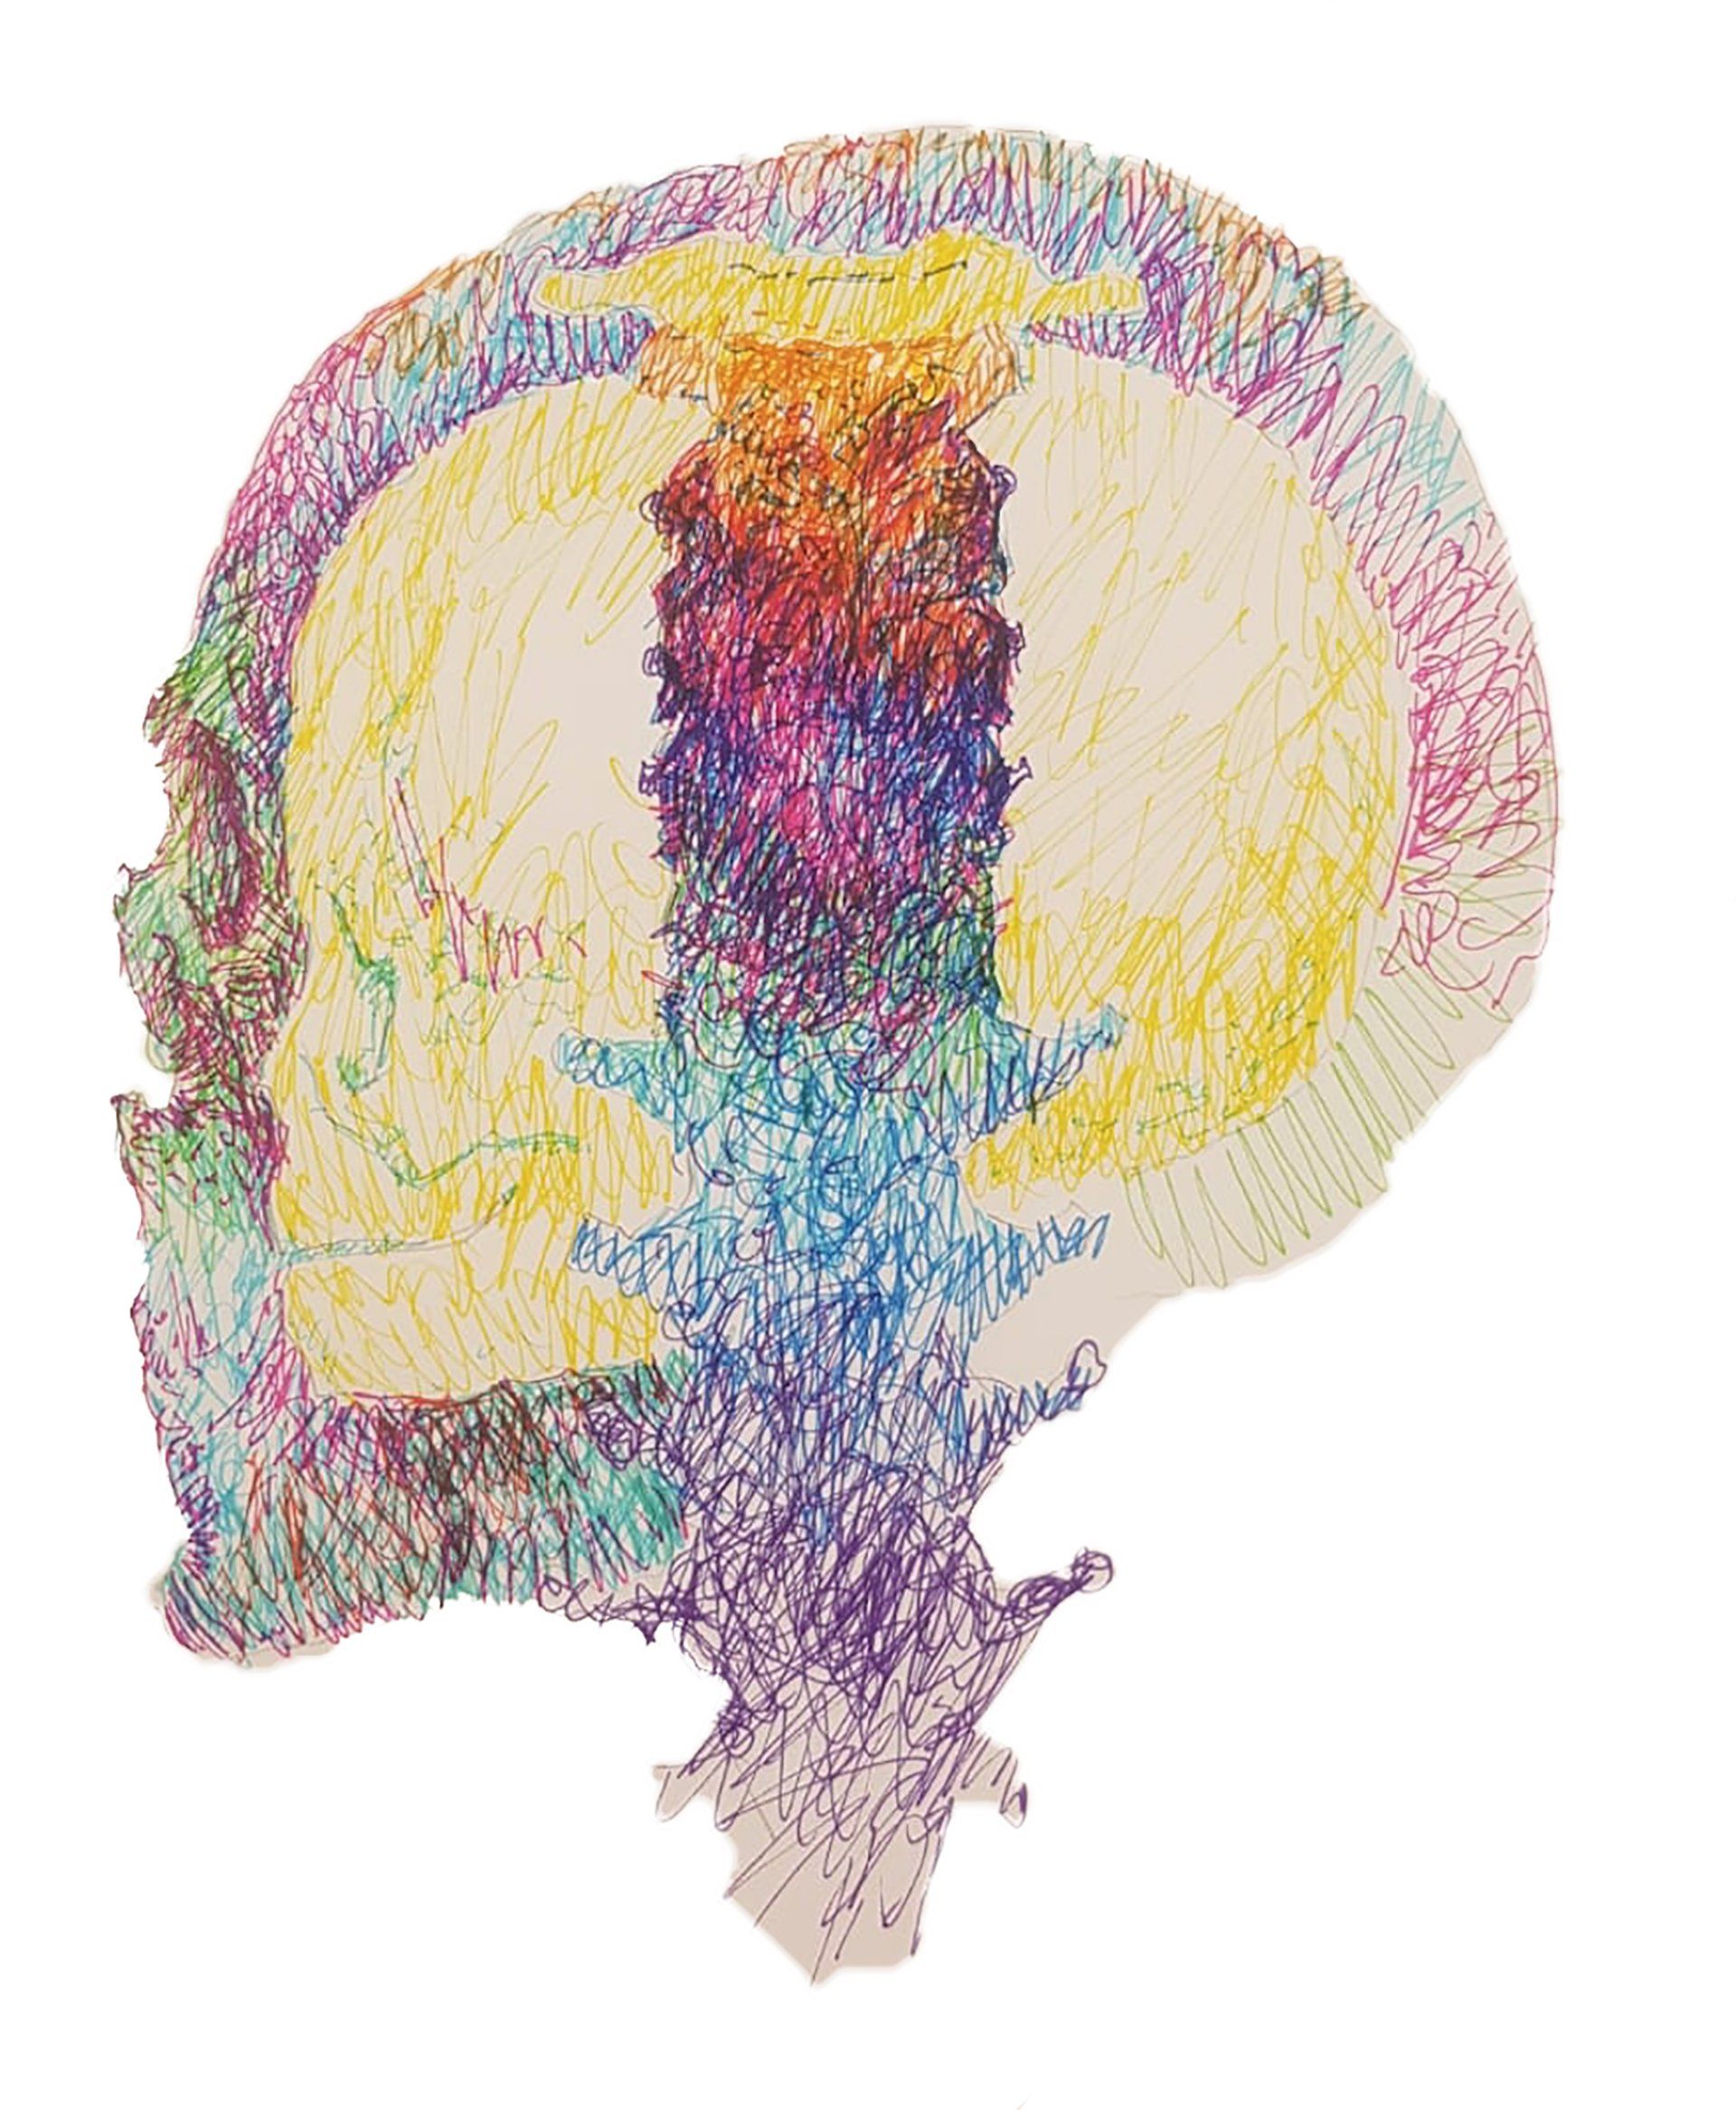

Predicting the survival of patients diagnosed with glioblastoma (GBM) is essential to guide surgical strategies and subsequent adjuvant therapies. Intraoperative ultrasound (ioUS) is a low-cost, versatile technique available in most neurosurgical departments. The images from ioUS contain biological information possibly correlated with the tumor's behavior, aggressiveness, and oncological outcomes. Today's advanced image processing techniques require a large amount of data. Therefore, we propose creating an international database aimed at sharing intraoperative ultrasound images of brain tumors. The acquired data must be processed to extract radiomic or texture characteristics from ioUS images. The rationale is that ultrasound images contain much more information than the human eye can process. Our main objective was to identify a relationship between these imaging characteristics and overall survival (OS) in GBM. The predictive models elaborated from this imaging technique will complement those already based on other sources, such as MRI and genetic and molecular analysis. Predicting survival using an intraoperative imaging technique that is affordable for most hospitals would greatly benefit patient management.